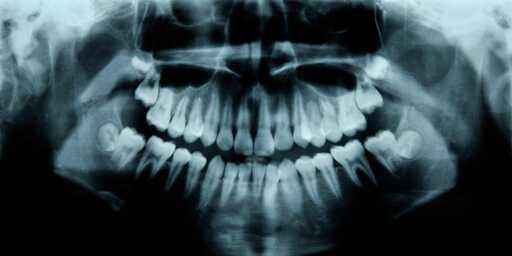

futurk@feddit.org to science@lemmy.worldEnglish · 13 days agoHumans Have a Third Set of Teeth. New Medicine May Help Them Grow.www.popularmechanics.comexternal-linkmessage-square24fedilinkarrow-up1128arrow-down120

arrow-up1108arrow-down1external-linkHumans Have a Third Set of Teeth. New Medicine May Help Them Grow.www.popularmechanics.comfuturk@feddit.org to science@lemmy.worldEnglish · 13 days agomessage-square24fedilink